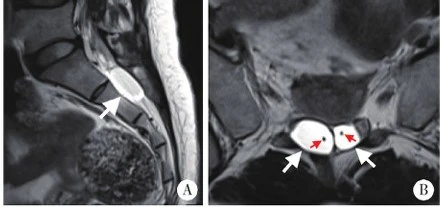

目前MRI是对神经根囊肿最具诊断价值的影像学检查。T1加权像:囊肿呈现边界清晰的低信号影(暗区),T2加权像:为明亮的高信号影(亮区),脂肪抑制序列(T2W/SPIR):骶管内脂肪信号被抑制,囊肿显示更加清晰。

更先进的磁共振脊髓水成像(MRM)能三维立体显示囊肿与神经根的解剖关系。典型表现是多个囊肿呈“葡萄串状”或“叠八字形”排列在神经根走行区,这种特征性表现让医生能准确判断囊肿的位置、大小和数量。